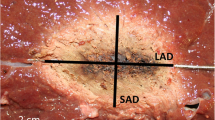

Image processing was performed in Vitrea Advanced Visualization software (Vital Images, Minnetonka, USA) to evaluate the size and shape of each ablation. Ablation size was measured in millilitres (mL) and derived from the images using a semi-automated segmentation tool with adaptive thresholding. The ablation diameter was recorded in three axes, as shown in Figure 2: a long-axis diameter (LAD) in plane with the needle insertion axis and two orthogonal short-axis diameters (SAD). The sphericity index (SI) was defined as the ratio between those diameters \(\frac{{\mathrm{SAD}}_{1}+{\mathrm{SAD}}_{2}}{2\mathrm{LAD}}\). An SI of 1 therefore denotes a perfectly spherical ablation, whereas a lower SI means that the ablation shape is more elliptical. Imaging parameters were acquired blinded from system and settings.